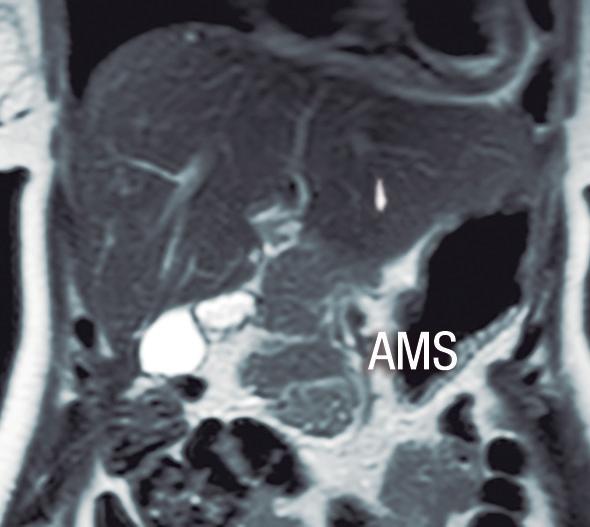

Páncreas Circumportal

El páncreas engloba a la vena mesentérica superior o vena porta, en lugar de rodear al duodeno como sucede en el páncreas anular (Figura 14). Tiene una prevalencia de hasta 2,5% según algunas series, por ende, no es tan infrecuente encontrarlo en estudios por imágenes. Se

A B

postula que su origen está relacionado con una anomalía en la rotación y fusión del brote ventral con el dorsal. Es una condición asintomática, pero cobra relevancia reconocerla e informarla en pacientes que serán sometidos a cirugía del páncreas, con el fin de reducir complicaciones, particularmente la fístula pancreática.25, 26

A) Resonancia magnética, secuencia T2, plano coronal. Se observa un páncreas “truncado”, con ausencia de tejido glandular a la izquierda del cuello (flecha), coincidente con una agenesia parcial del brote embriológico dorsal. La cabeza de flecha nos muestra a la porción cefálica prominente, redondeada. B) Resonancia magnética, secuencia T1 con contraste, plano axial. Flecha: Limite de finalización de la glándula, a la izquierda de la arteria mesentérica superior. Cabeza de flecha: Porción cefálica prominente, redondeada. C) Resonancia magnética, secuencia T1 con contraste, plano axial, corte más caudal. Las flechas muestran hipertrofia relativa del proceso uncinado (brote ventral), el cual llega a ubicarse por detrás de los vasos mesentéricos superiores, incluso superando el plano de la arteria. AMS: arteria mesentérica superior.

A) Resonancia magnética, secuencia T1 sin contraste, plano axial. Tejido pancreático con típica señal hiperintensa en secuencia de ponderación tisular T1 (cabezas de flecha), rodeando a la vena porta (VP). B) Resonancia magnética, secuencia T1 con contraste, fase portal, plano axial. VP: vena porta, VE: vena esplénica, AMS: arteria mesentérica superior.